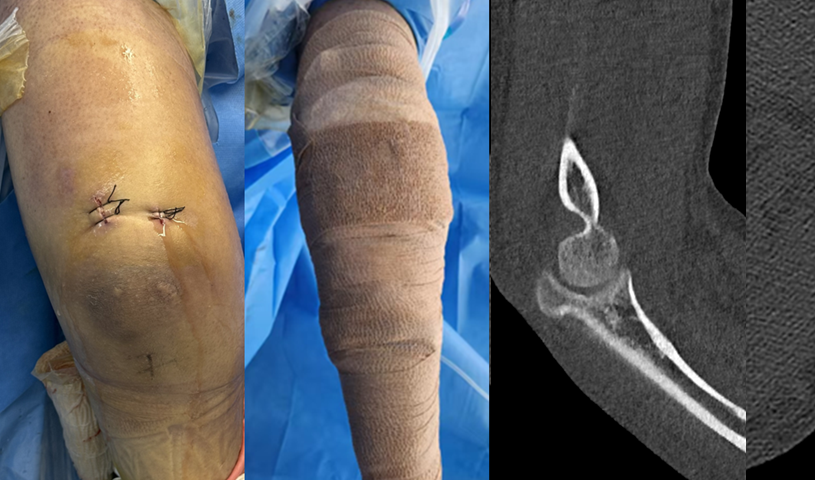

患者朱先生,33岁,1月前骑车摔倒致右肘关节疼痛、肿胀及活动受限,他感到肘关节“伸也伸不直,弯也弯不了”。来到我院查体,右肘关节的活动度只有屈曲90°、伸直30°,活动范围明显受限。术前的影像学检查提示:右尺骨鹰嘴骨折,撕脱的骨碎片游离并卡压于关节间隙。这些“深藏不露”的碎片,正是导致朱先生肘关节持续卡压、活动障碍的“罪魁祸首”。结合病史、查体及影像学检查,诊断为右尺骨鹰嘴骨折伴游离体卡压。

术前CT检查提示关节腔内游离骨折块(红色圆圈)